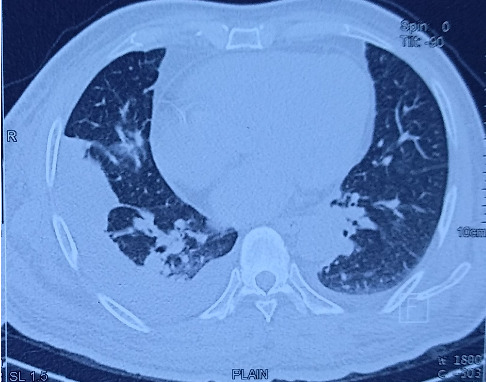

Background: Staphylococcal infection is a common bacterial disease with common clinical features. Untreated infection, especially in immunosenescence cases, can affect other organs. This can lead to multiorgan dysfunction and cause increased morbidity and mortality. Unlike commonly presented features of pneumonia, dissemination of infection can pose diagnostic and therapeutic enigma. Therefore, any such presentation in common clinical practice can yield a conundrum of diagnoses. Case Report: A 69-year-old elderly male presented to the Emergency Department with acute onset encephalopathy. Historically, cues were limited, and evaluation was negated for acute cerebrovascular event or seizure. Laboratory findings were suggestive of a severe sepsis. While clinical medicine workup and diagnostic dilemma were ongoing, possible sources of the sepsis were thoroughly sought including range of infectious causes. This patient's presentation was one of its kind: staphylococcal bacteremia seeding to cause pneumonia and unusual epidural abscess in due course of illness. Conclusion: The health outcome of the critically ill especially elderly patients depends mostly on the importance of clinical medicine to address the diagnostic enigma and virtue of supportive care delivered. Staphylococcus aureus infections are capable of developing distant infectious foci, as highlighted in this case, and that the clinician should be alert to this possibility. This particular case firmly posits an admonition for clinicians and the importance of clinical medicine for critical reasoning to improve the patient outcome.